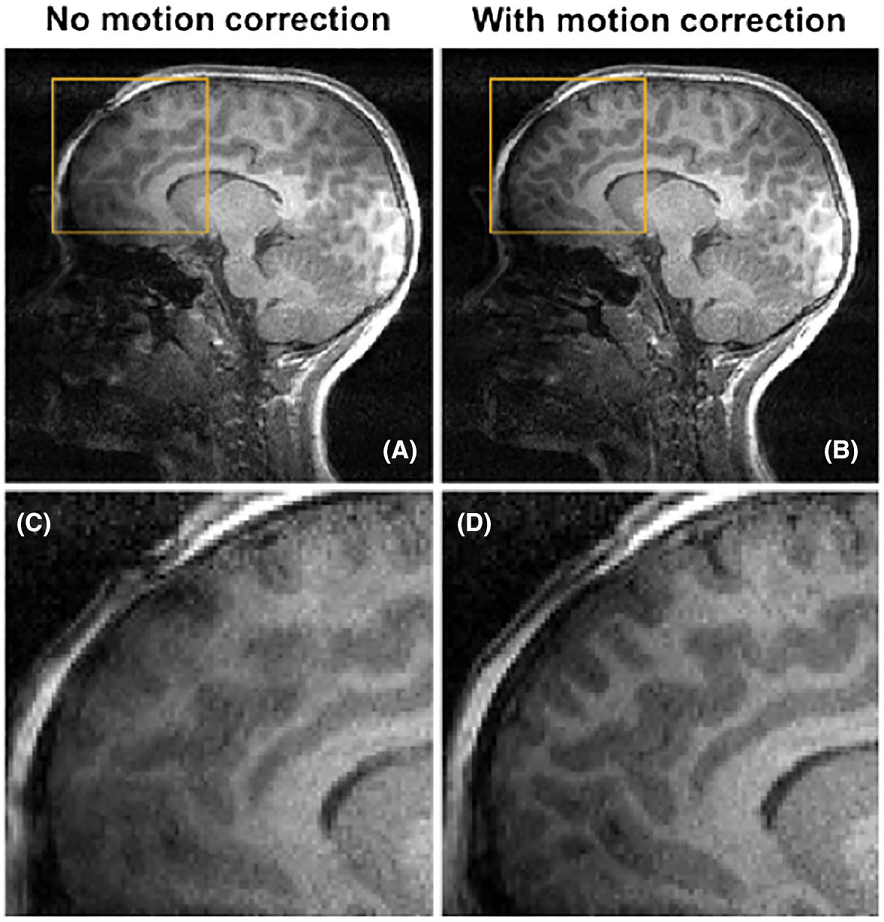

The following image was taken from the abstract: Retrospective correction of head motion using measurements from an electromagnetic tracker. It shows substantialy lower artifact levels in image B where retrospective motion correction was used vs image A which is the uncorrected image. Images C and D are zoomed in areas of A and B respectively. Image D shows reduced blurring and improved gray/white matter differentiation.